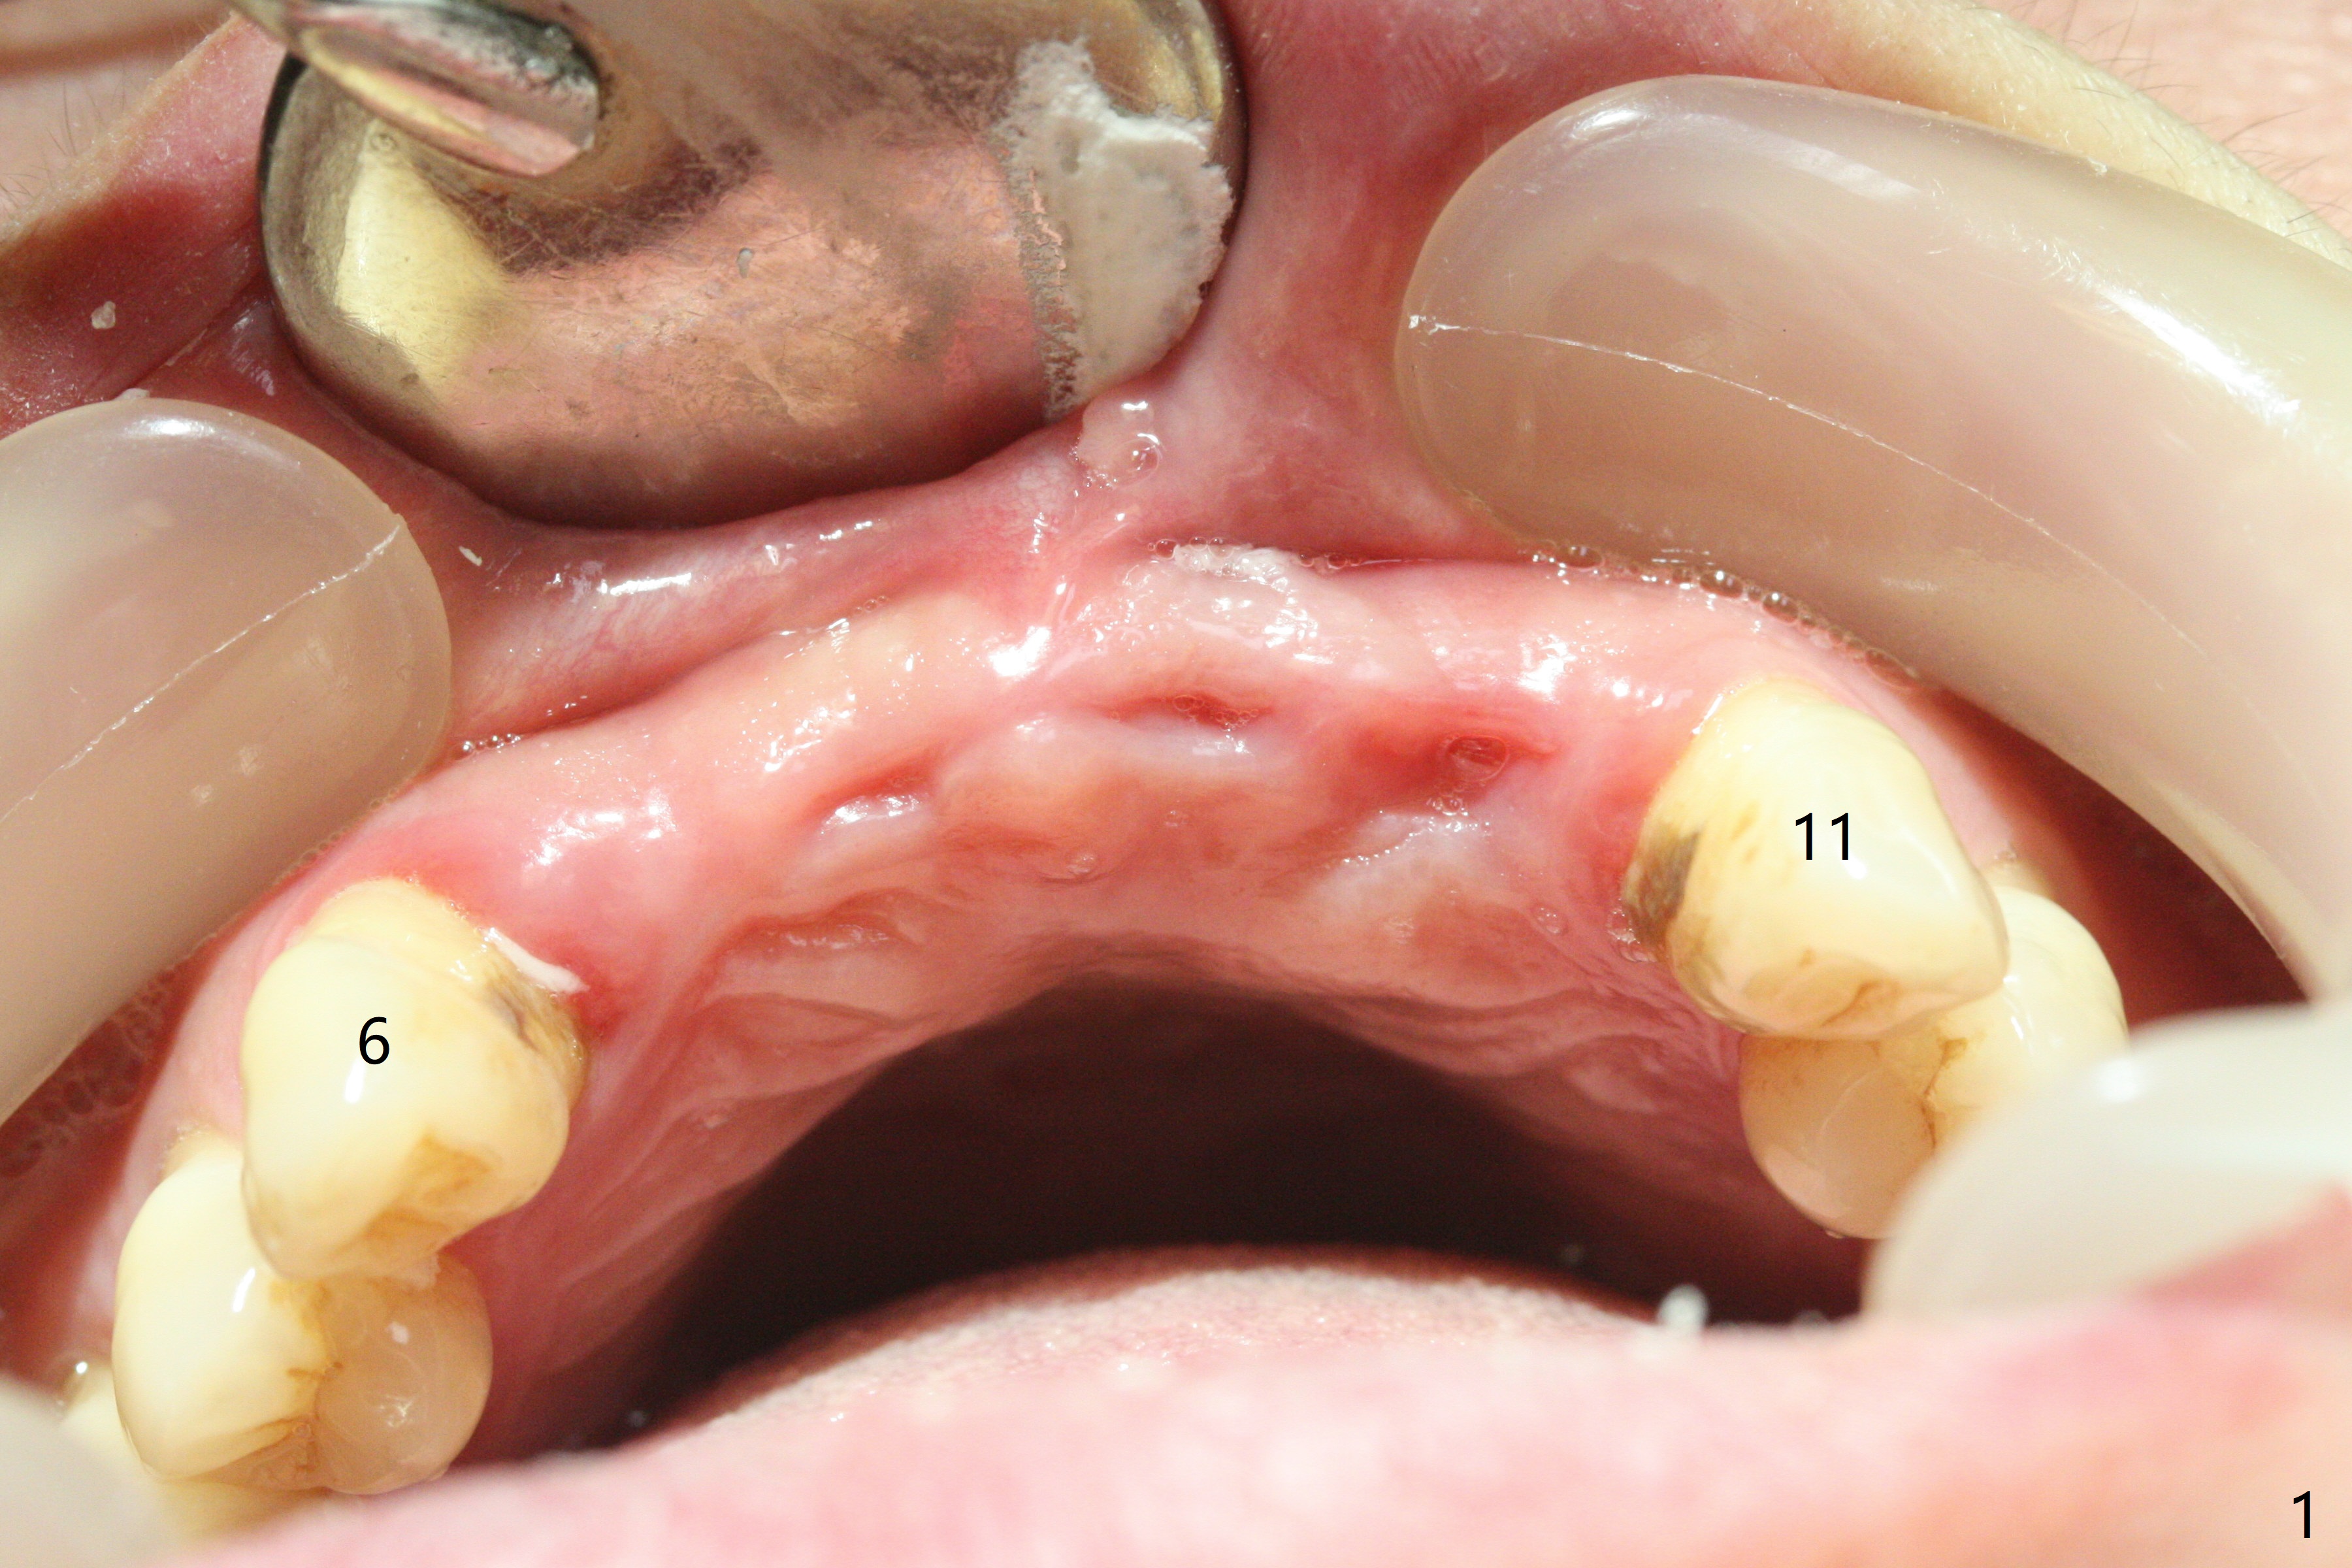

Although the ridge of the maxillary anterior ridge looks moderate in width (Fig.1), the bone is ~4 mm buccopalatally. Suction down surgical stent (Fig.2') made from the lab-fabricated provisional (Fig.2) will be used to check the position and trajectory of osteotomies. PAs taken after initial osteotomies (1.2 mm drill) show those at the central incisors tend to be mesial (close to the Incisive Canal *), while those at the lateral incisor sites distal (Fig.3,4). After adjustment, the position and trajectory of the osteotomies are acceptable (Fig.5,6). To reduce the chance of perforating the Incisive Canal (Fig.3,4 *), 2.5 mm 1-piece implants are inserted with >40 Ncm (Fig.7,8). After deep placement of the implants, Vanilla graft is placed at the crest (Fig.9,10 *). An immediate splinted provisional is fabricated from the suction down stent. The gingiva is healthy around the provisional (Fig.11) and the implants (Fig.12,13) 1 month postop. The provisional is adjusted monthly so that the interdental papillae can be elongated. No bone resorption is observed 6 months postop (Fig.14,15). Crowns are cemented 8 months postop (Fig.16-18). The keratinized gingiva appears to have formed the abutments 8 months postop immediately pre-cementation (Fig.19).